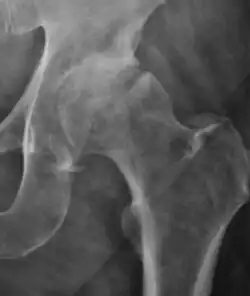

Projectional radiography ("X-ray") is the first imaging technique of choice in hip pain, not only in older people with suspected osteoarthritis but also in young people without any such suspicion. In this case plain radiography allows categorization as normal hip or dysplastic hip, or with impingement signs, pincer, cam, or a combination of both.[1]

X-Ray

Projectional radiography ("X-ray") is currently useful not only in older people in whom osteoarthritis of the hip is suspected but also in younger people without osteoarthritis, who are being evaluated for femoroacetabular impingement (FAI) or hip dysplasia.[1]

Plain radiography allows us to categorize the hip as normal or dysplastic or with impingement signs (pincer, cam, or a combination of both). Besides these, pathologic processes like osteoarthritis, inflammatory diseases, infection, or tumors can also be identified (Figure 1).[1]

- Osteoarthritis

In adults, one of the main indications for radiographs is the detection of osteoarthritic changes (Figure 1(e)). Nevertheless, radiographs usually detect advanced osteoarthritis that can be graded according to the Tönnis classifications. The grading system ranges from 0 to 3, where 0 shows no sign of osteoarthritis. Intermediate grade 1 shows mild sclerosis of the head and acetabulum, slight joint space narrowing, and marginal osteophyte lipping. Grade 2 presents with small cysts in the femoral head or acetabulum, moderate joint space narrowing, and moderate loss of sphericity of the femoral head. Grade 3 is the severest form of osteoarthritis, which manifests as severe narrowing of the joint space, large subchondral cyst with productive bone changes that may lead to deformity of the bone components of the joint, while secondary osteoarthritis due to calcium pyrophosphate deposition can be diagnosed when calcification of hyaline cartilage and fibrocartilage is detected.[1]

There are other pathological conditions that can affect the hip joint and radiographs help to make the appropriate diagnosis. Acute bacterial septic arthritis can be diagnosed by radiographs when a fast regional osteoporosis and destructive monoarticular process develops (Figure 1(f)). In case of tuberculous or brucella arthritis it is manifested as a slow progressive process, and diagnosis may be delayed.[1]